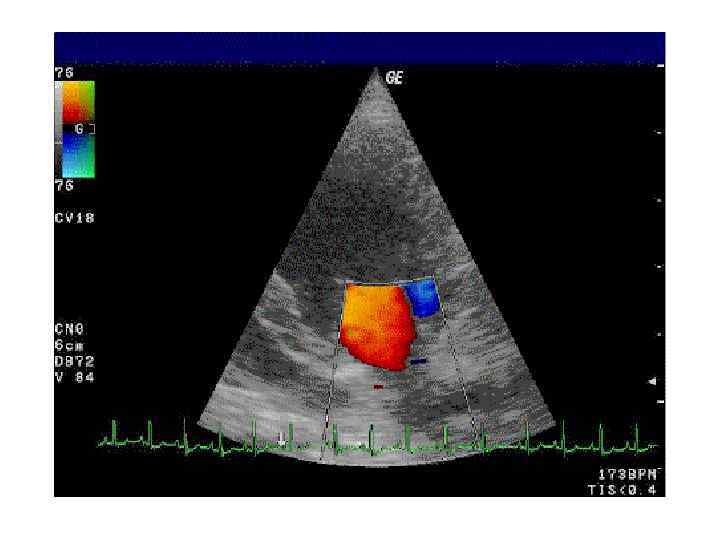

Цветовой допплер (Color Doppler) • выделение на эхограмме цветом (цветное картирование) характера кровотока в области интереса. • Кровоток к датчику принято картировать красным цветом, от датчика - синим цветом. • Турбулентный кровоток картируется сине-зеленожелтым цветом. • Цветовой допплер применяется для исследования кровотока в сосудах, в эхокардиографии.

Цветовой допплер (Color Doppler) • выделение на эхограмме цветом (цветное картирование) характера кровотока в области интереса. • Кровоток к датчику принято картировать красным цветом, от датчика - синим цветом. • Турбулентный кровоток картируется сине-зеленожелтым цветом. • Цветовой допплер применяется для исследования кровотока в сосудах, в эхокардиографии.

Цветовой допплер • Кровоток к датчику принято картировать красным цветом, • от датчика - синим цветом. • Турбулентный кровоток картируется сине-зелено-желтым цветом.

Цветовой допплер • Кровоток к датчику принято картировать красным цветом, • от датчика - синим цветом. • Турбулентный кровоток картируется сине-зелено-желтым цветом.

• Митральный клапан, регургитация, цветной допплер, MR (videо).

• Митральный клапан, регургитация, цветной допплер, MR (videо).

• Сердце, апикальный доступ, 4 -камерная позиция, цветной допплер.

• Сердце, апикальный доступ, 4 -камерная позиция, цветной допплер.